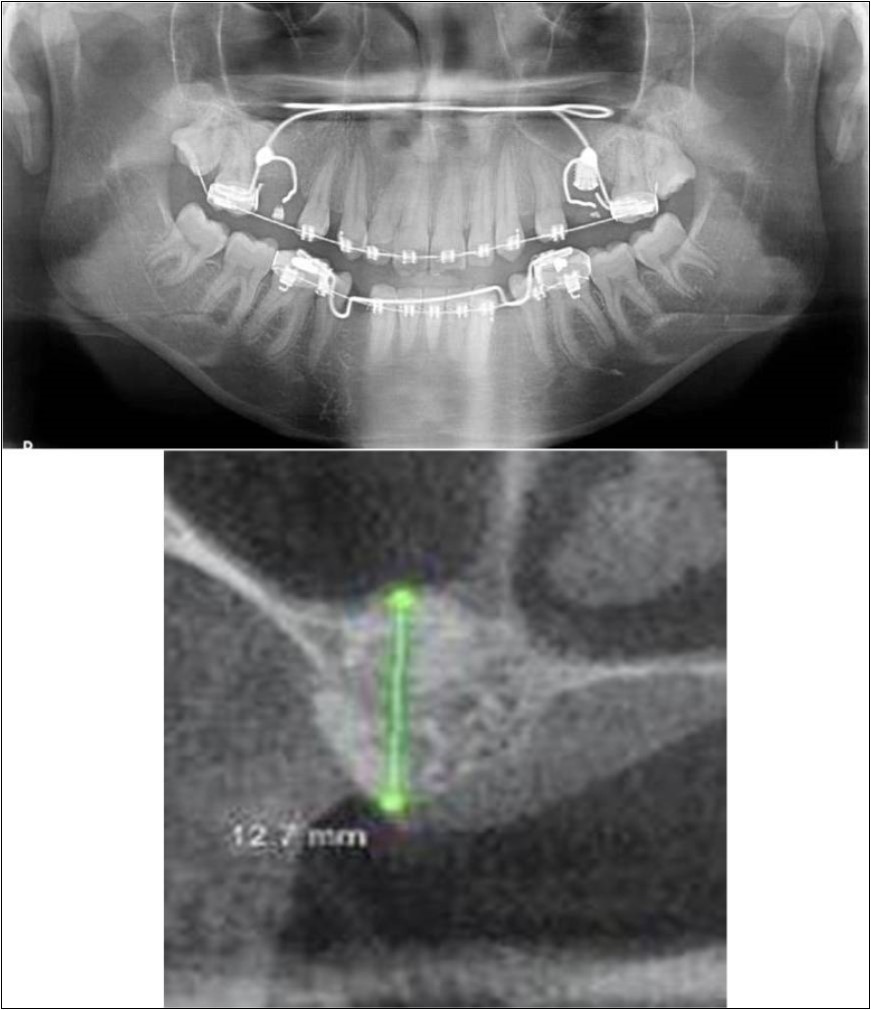

A 19 years old young female patient reported to the Department of Oral and Maxillofacial Surgery, D.A.P.M.R.V Dental College and Hospital seeking options for replacement of her missing right and left upper first molars with a fixed prosthesis as she was uncomfortable with the removable partial denture i.r.t 16 and 26. The teeth were extracted 6 months ago because of gross loss of crown structure and poor prognosis for root canal treatment. Patient was also undergoing fixed orthodontic treatment for proclined upper anteriors. Patient did not give history of any existing sinus pathologies. All possible rehabilitative options were explained to the patient and a treatment plan of replacement of missing teeth with implant supported prosthesis using two dental implants was finalized.

Clinical and Radiological Assessment:

1.Partially edentulous maxillary arch with missing 16 and 26;

2.Increased pneumatisation of right and left maxillary sinus;

3.Height of available bone-

16 region: 6.5mm;

26 region: 6.2mm;

4.Transverse thickness of available bone (CBCT evaluation)-

16 region: 8.3mm;

26 region: 10.5mm;

5.Fixed orthodontic appliance;

6.Inter-ridge space adequate to place implant (11mm).

Treatment:

Patient underwent the procedure of indirect sinus elevation using sinus osteotomes in relation to 26 region. Calcium phosphosilicate putty was dispensed as the graft material through the crestal osteotomy site to maintain the elevated sinus membrane followed by placement of 5 x 10mm dental implant under local anaesthesia and strict aseptic protocols. The implant was allowed to osseo-integrate for a period of six months during which the patient was followed-up periodically and was assessed for peri-implantitis, crestal bone loss and mobility. Patient was taken-up for direct sinus elevation via lateral window approach for sinus augmentation i.r.t 16 region. Under aseptic conditions and local anaesthesia, lateral wall of maxilla was exposed after muco-periosteal flap elevation. A window was created of 1cm diameter corresponding to apical aspect of 16. Sinus membrane was identified and elevated using sinus elevators and reamers without perforating the lining. Once the sinus membrane was elevated, phosphosilicate putty was dispensed through the lateral osteotomy site as the graft material to achieve an augmentation of 1cm assessed clinically and confirmed using post-operative OPG. At the end of 6 months, a repeat CBCT scan was advised to evaluate the increase in bone height. (Figure 13a,b, pre-treatment; Figure 14a,b, post-treatment)

Figure 13.(a,b) Pre-treatment OPG and cross section of CBCT showing residual alveolar bone height for Case No.4;

Figure 14.(a,b) Post-treatment OPG and cross section of CBCT showing residual alveolar bone height for Case No.4;